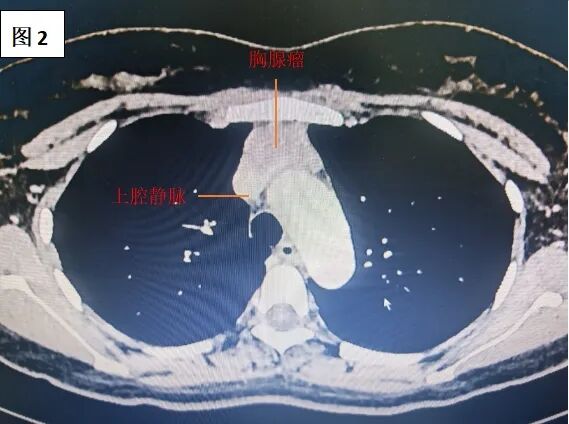

胸部强化CT显示,胸腺瘤体积大,已侵犯左无名静脉并累及上腔静脉,血管管腔严重受压。如果不及时手术,肿瘤继续侵犯更多脏器,可能引发上腔静脉综合征,导致头面部水肿、呼吸困难,甚至危及生命。